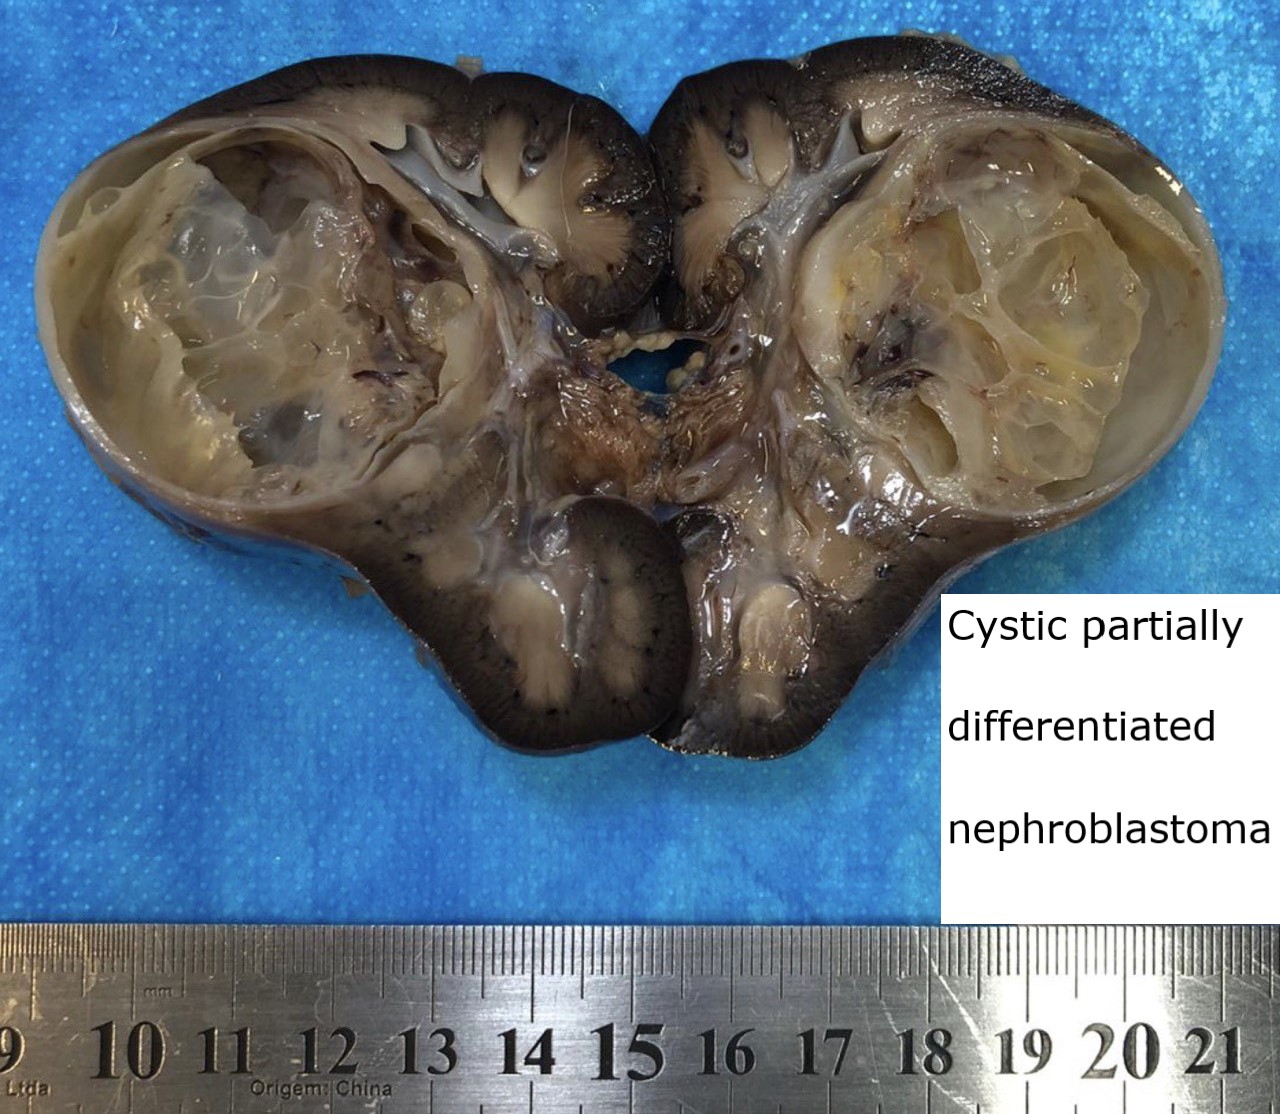

Gross description

- Typically, a large multilocular cystic tumor (mean diameter of 10 cm)

- Thin or variable sized septa

- Well circumscribed

- No expansive nodules

- Reference: J Postgrad Med 2006;52:45

Gross images